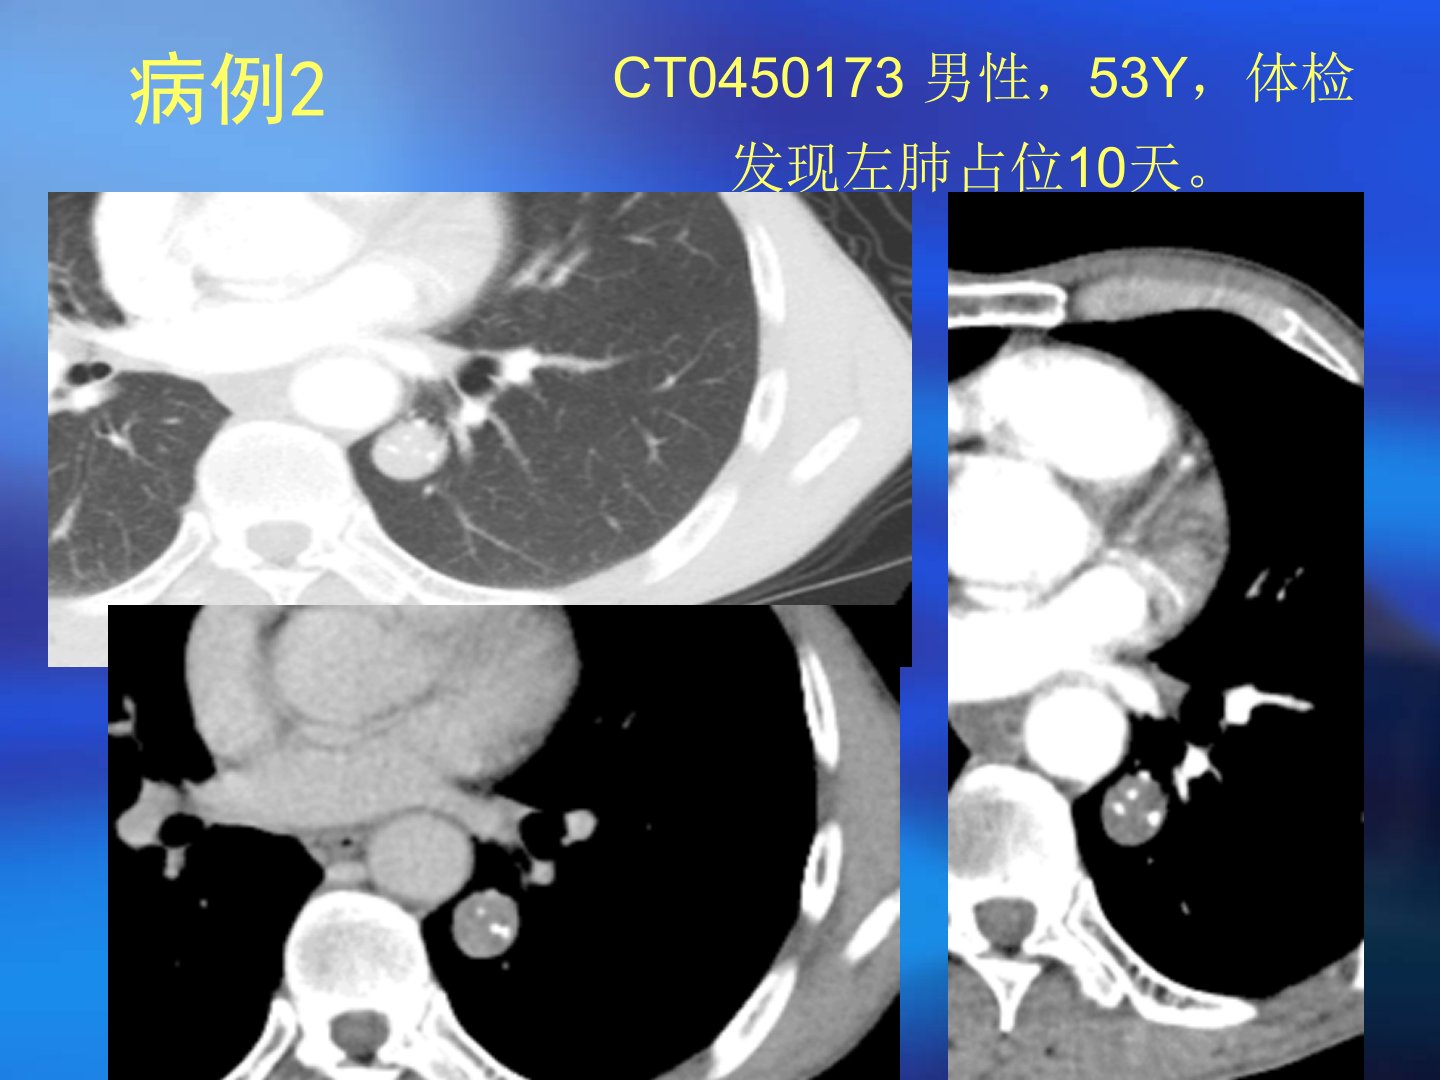

本文汇报了多例肺部占位病例并重点讨论了肺部错构瘤。错构瘤是机体器官内正常组织在发育中出现错误组合导致的类瘤样畸形1904年由德国病理学家albrecht首次提出目前尚无恶变报道。病理特点为正常组织的不正常组合排列构成主要是软骨、脂肪等。根据发生部位错构瘤可分为中央型和周围型WHO将其分为三类。错构瘤好发于40岁以上男性多生长在肺部周边一般无症状刺激或压迫支气管时才会出现相应症状。CT表现上中央型表现为大支气管腔内结节状病变周围型则呈肺内结节样。其CT特点包括边缘光滑、多呈圆形或类圆形、多小于5cm、典型表现为肿块内有脂肪密度区等。鉴别诊断方面需与肺癌、结核瘤、硬化性血管瘤、软骨瘤、转移瘤等区分。